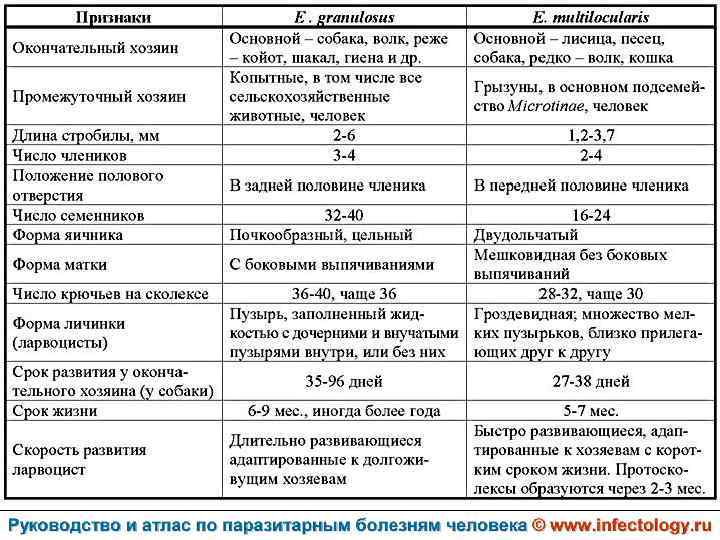

Цистный эхинококкоз (цистный гидатидоз) (шифр по МКБ 10 - B 67. 0 -4) – зоонозный биогельминтоз, характеризующийся хроническим течением, образованием кист и деструктивным поражением печени, легких и других органов.

Альвеолярный (многокамерный) эхинококкоз человека (альвеолярный гидатидоз) (шифр по МКБ 10 - B 67. 5 -7) – зоонозный биогельминтоз, характеризующийся чрезвычайно тяжелым хроническим течением, первичным опухолевидным поражением печени, нередко с метастазами в головной мозг и легкие, а также во многие другие органы. Заболевание часто заканчивается летально.